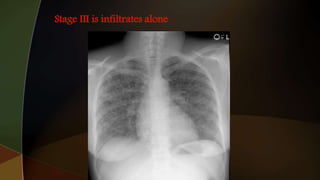

1. hilar adenopathy alone

2. hilar adenopathy plus infiltrates;

3. infiltrates alone;

4. fibrosis

1. hilar adenopathyalone 2. hilar adenopathy plus infiltrates; 3. infiltrates alone; 4. fibrosis